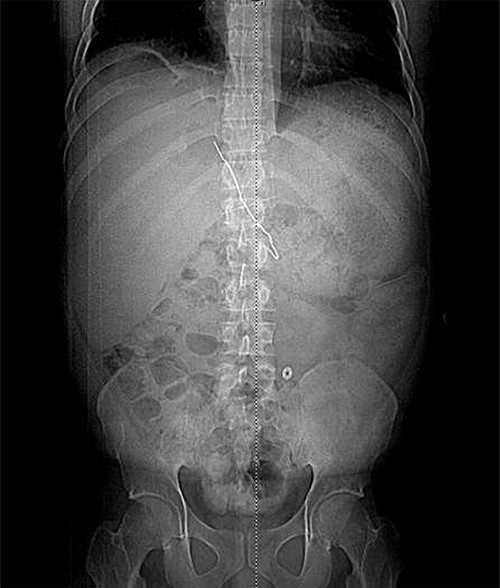

The patient presented after ingestion of an open paperclip and insertion of a sewing needle into his ventral hernia ~4 months prior. He presented with fever, tachycardia and abdominal pain, but a benign abdominal exam, noting only mild tenderness over his large, reducible ventral hernia. A computed tomography (CT) of the abdomen and pelvis showed a 10-cm metallic foreign body extending from the mid transverse colon to the left hepatic lobe with an intrahepatic abscess measuring 9.1 x 7.3 cm (Figs 1–3). In addition, there were two other metallic foreign bodies: one extraluminal in the left upper quadrant, which was stable from prior imaging, and a subcutaneous foreign body above the hernia contents. Blood cultures grew streptococcus intermedius and he was started on broad spectrum antibiotics (piperacillin–tazobactam). The case was discussed with Interventional Radiology (IR) and deemed reasonable for attempt at percutaneous abscess drainage and trans-hepatic foreign body retrieval.

CT view of metallic foreign body within the liver abscess cavity.